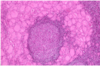

Know this image.

yeah.